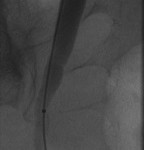

Access was gained from the back into a dilated posterior calyx of each kidney and secured with a sheath. Antegrade pyelogram on each side revealed marked ureteral and calyceal dilation due to complete obstruction of the distal ureter. A wire was advanced into the urinary bladder past the obstruction, which was dilated with a non-compliant balloon when it resisted the deployment of a nephroureteral stent. The stent was successfully deployed after the balloon dilation.

If obstructions are easy to cross, internal ureteral stents may be placed across them, with one end of the stent in the renal pelvis and the other in the urinary bladder. The stents should be changed periodically through the urethra by urologists or interventional radiologists. Sometimes, as in the patient whose images are displayed above, the obstruction must be predilated to permit insertion of the ureteral stents. Alternatively, a drainage catheter called a nephrostomy catheter can be deployed into the renal pelvis to drain urine into a bag attached to it without crossing the obstruction.